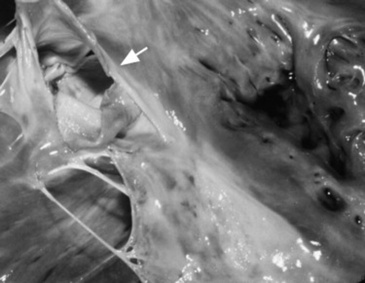

Necropsy Findings

Aneurysms are detected grossly as dilations of the involved blood vessel. Aneurysms of the sinus of Valsalva are characterized by an absent tunica media in the wall of the aorta, causing the aneurysmal dilation.205,208 Rupture of a sinus of Valsalva aneurysm may occur into the right atrium, right ventricle (Fig. 30-29), or interventricular septum, resulting in an aortic cardiac fistula and volume overload.205-209 Rupture through the tricuspid valve or chordae tendineae may also occur. Subendocardial dissection of blood down the interventricular septum may occur, with subsequent rupture into the left ventricle and of the mitral chordae tendineae also reported. Aneurysms of the major vessels leaving the heart may involve more than one vessel by dissection and hemorrhage. Aneurysms may contain thrombi or parasites, and there may be evidence of embolic showering of thrombi into peripheral vessels or other organ systems, especially the lungs. Histologically there may be necrosis and inflammation at the site of the aneurysm with foci of mineralization.

image

Fig. 30-29 Ruptured sinus of Valsalva aneurysm in a horse with acute onset of colic and right-sided congestive heart failure. The large aneurysm (arrow) ruptured through the tricuspid valve, creating an aortic-cardiac fistula.